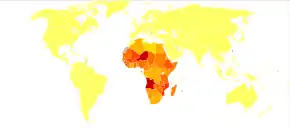

Schistosomiasis affected about 236.6 million people worldwide in 2019.[12] An estimated 4,400 to 200,000 people die from it each year.[7][8] The disease is most commonly found in Africa, Asia, and South America.[5] Around 700 million people, in more than 70 countries, live in areas where the disease is common.[7][13] In tropical countries, schistosomiasis is second only to malaria among parasitic diseases with the greatest economic impact.[14] Schistosomiasis is listed as a neglected tropical disease.[15]

The disease is found in tropical countries in Africa, the Caribbean, eastern South America, Southeast Asia, and the Middle East. S. mansoni is found in parts of South America and the Caribbean, Africa, and the Middle East; S. haematobium in Africa and the Middle East; and S. japonicum in the Far East. S. mekongi and S. intercalatum are found locally in Southeast Asia and central West Africa, respectively.

In 2010, approximately 238 million people were infected with schistosomiasis, 85 percent of whom live in Africa.[73] An earlier estimate from 2006 had put the figure at 200 million people infected.[74] As of the latest WHO record, 236.6 million people were infected in 2019.[12] In many of the affected areas, schistosomiasis infects a large proportion of children under 14 years of age. An estimated 600 to 700 million people worldwide are at risk from the disease because they live in countries where the organism is common.[7][72] In 2012, 249 million people were in need of treatment to prevent the disease.[75] This likely makes it the most common parasitic infection with malaria second and causing about 207 million cases in 2013.[72][76]